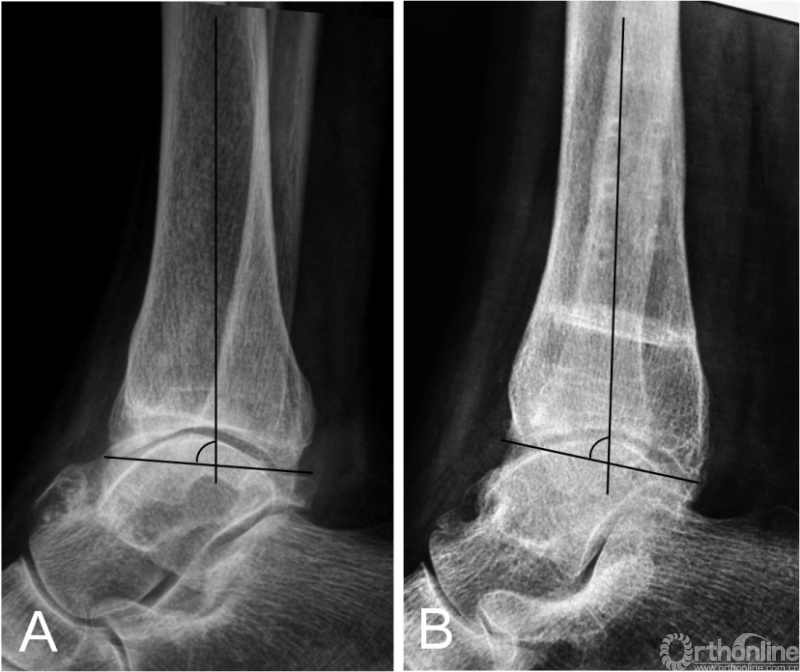

踝上截骨的主要目标之一就是矫正冠状面内翻畸形,即TAS角。临床研究指出,TAS的平均矫正程度从8.5~14.5°不等[6-21]。而对于踝关节OA患者矢状面TLS角为何会减小目前仍无定论[20,21]。本研究的TSA角在术前与术后未获得显著性差异,这可能与部分患者术前踝关节前侧存在显著骨赘有关(图4),因此术前的TLS测量常不能反映真实的TLS情况。因此,我们认为除非存在显著改变,术中无需刻意的去矫正TLS角。关于TT角在踝上截骨术中的意义目前争论最为激烈,研究报道间的差异性较大。一些作者指出,术后TT角得到显著矫正[8,11,13,16,17];然而,一些作者却强调踝上截骨并无矫正TT角的能力[6,12,14,21]。Tanaka等[21]报道的病例中,所有术前TT≥10°的患者,术后均未矫正至正常。Lee等[14]指出,术前TT角与术后TT角有相关性,他们认为在术前TT≥7.3°的患者,应放弃踝上截骨术。然而,在我们的患者中,67%(4/6)术前TT≥10°的患者,术后恢复到正常范围(TT≤4°[12])。Mann等[15]报道,在术后TT≥10°的患者,依然可以获得较好的临床功能。Kim等[11]则报道,没有任何影像学指标与术后功能有直接相关性。我们认为,在非终末期内翻型踝关节OA患者,通过踝上截骨来矫正负重力线及改善关节适配性是值得的,即使对于TT较大的患者。因为踝上截骨可以关节接触压强得到重新分布,外移踝关节机械轴[28],延缓甚至逆转OA的进程;甚至通过术后负重改变,使TT重新恢复至正常范围(图5)。我们认为,影像学的改变有时是需要时间的,正如OA的形成原因。Cheng等[7]报道,所有患者在随访时内侧间隙逐渐增宽,且常需要1年以上时间才能使踝关节间隙改善至理想程度。

图4 术前踝关节侧位X线片提示踝前骨赘形成,胫骨侧位关节面角为85°(4A);行关节清理及踝上截骨术后X线提示胫骨侧位关节面角为81°(4B)。